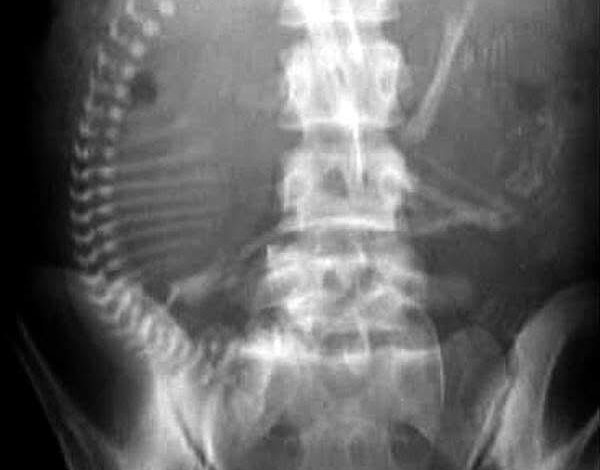

ورغم إنكار المريضة وعدم وجود زواج، قرر الطبيب افتراض حسن النية، والبدء من التشخيص الطبي المنطقي، فطلب أشعة سينية على البطن بوضعيات مختلفة، لاشتباه انسداد معوي، مع وضع في الاعتبار احتمال أن تكون في حالة ولادة كاملة، وأن الجنين مكتمل النمو ولن يتأثر كثيرًا بجرعة الأشعة في تلك اللحظة الحرجة.

جاءت نتيجة الأشعة صادمة وواضحة، هيكل عظمي كامل لجنين داخل الرحم.